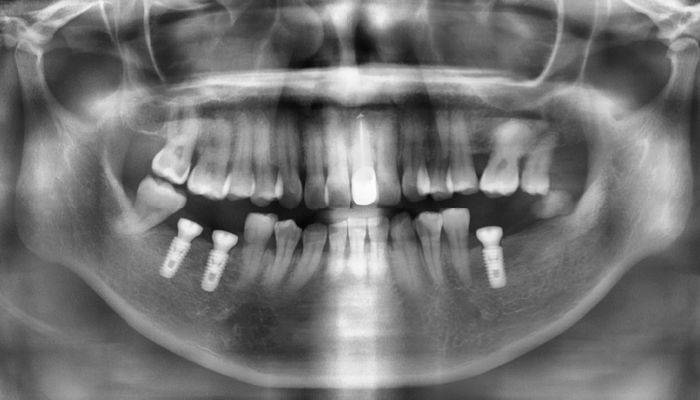

내비게이션 임플란트 수술

김OO님 전후사진 / 치료 기간 : 8주 / 식립갯수 : 전악

내비게이션 임플란트 수술

고OO님 전후사진 / 치료 기간 : 12주 / 식립갯수 : 11개

내비게이션 임플란트 수술

남OO님 전후사진 / 치료 기간 : 8주 / 식립갯수 : 10개

내비게이션 임플란트 수술

김OO님 전후사진 / 치료 기간 : 6주 / 식립갯수 : 3개

상악동 거상술 임플란트 수술

김OO님 전후사진 / 치료 기간 : 16주 / 식립갯수 : 2개